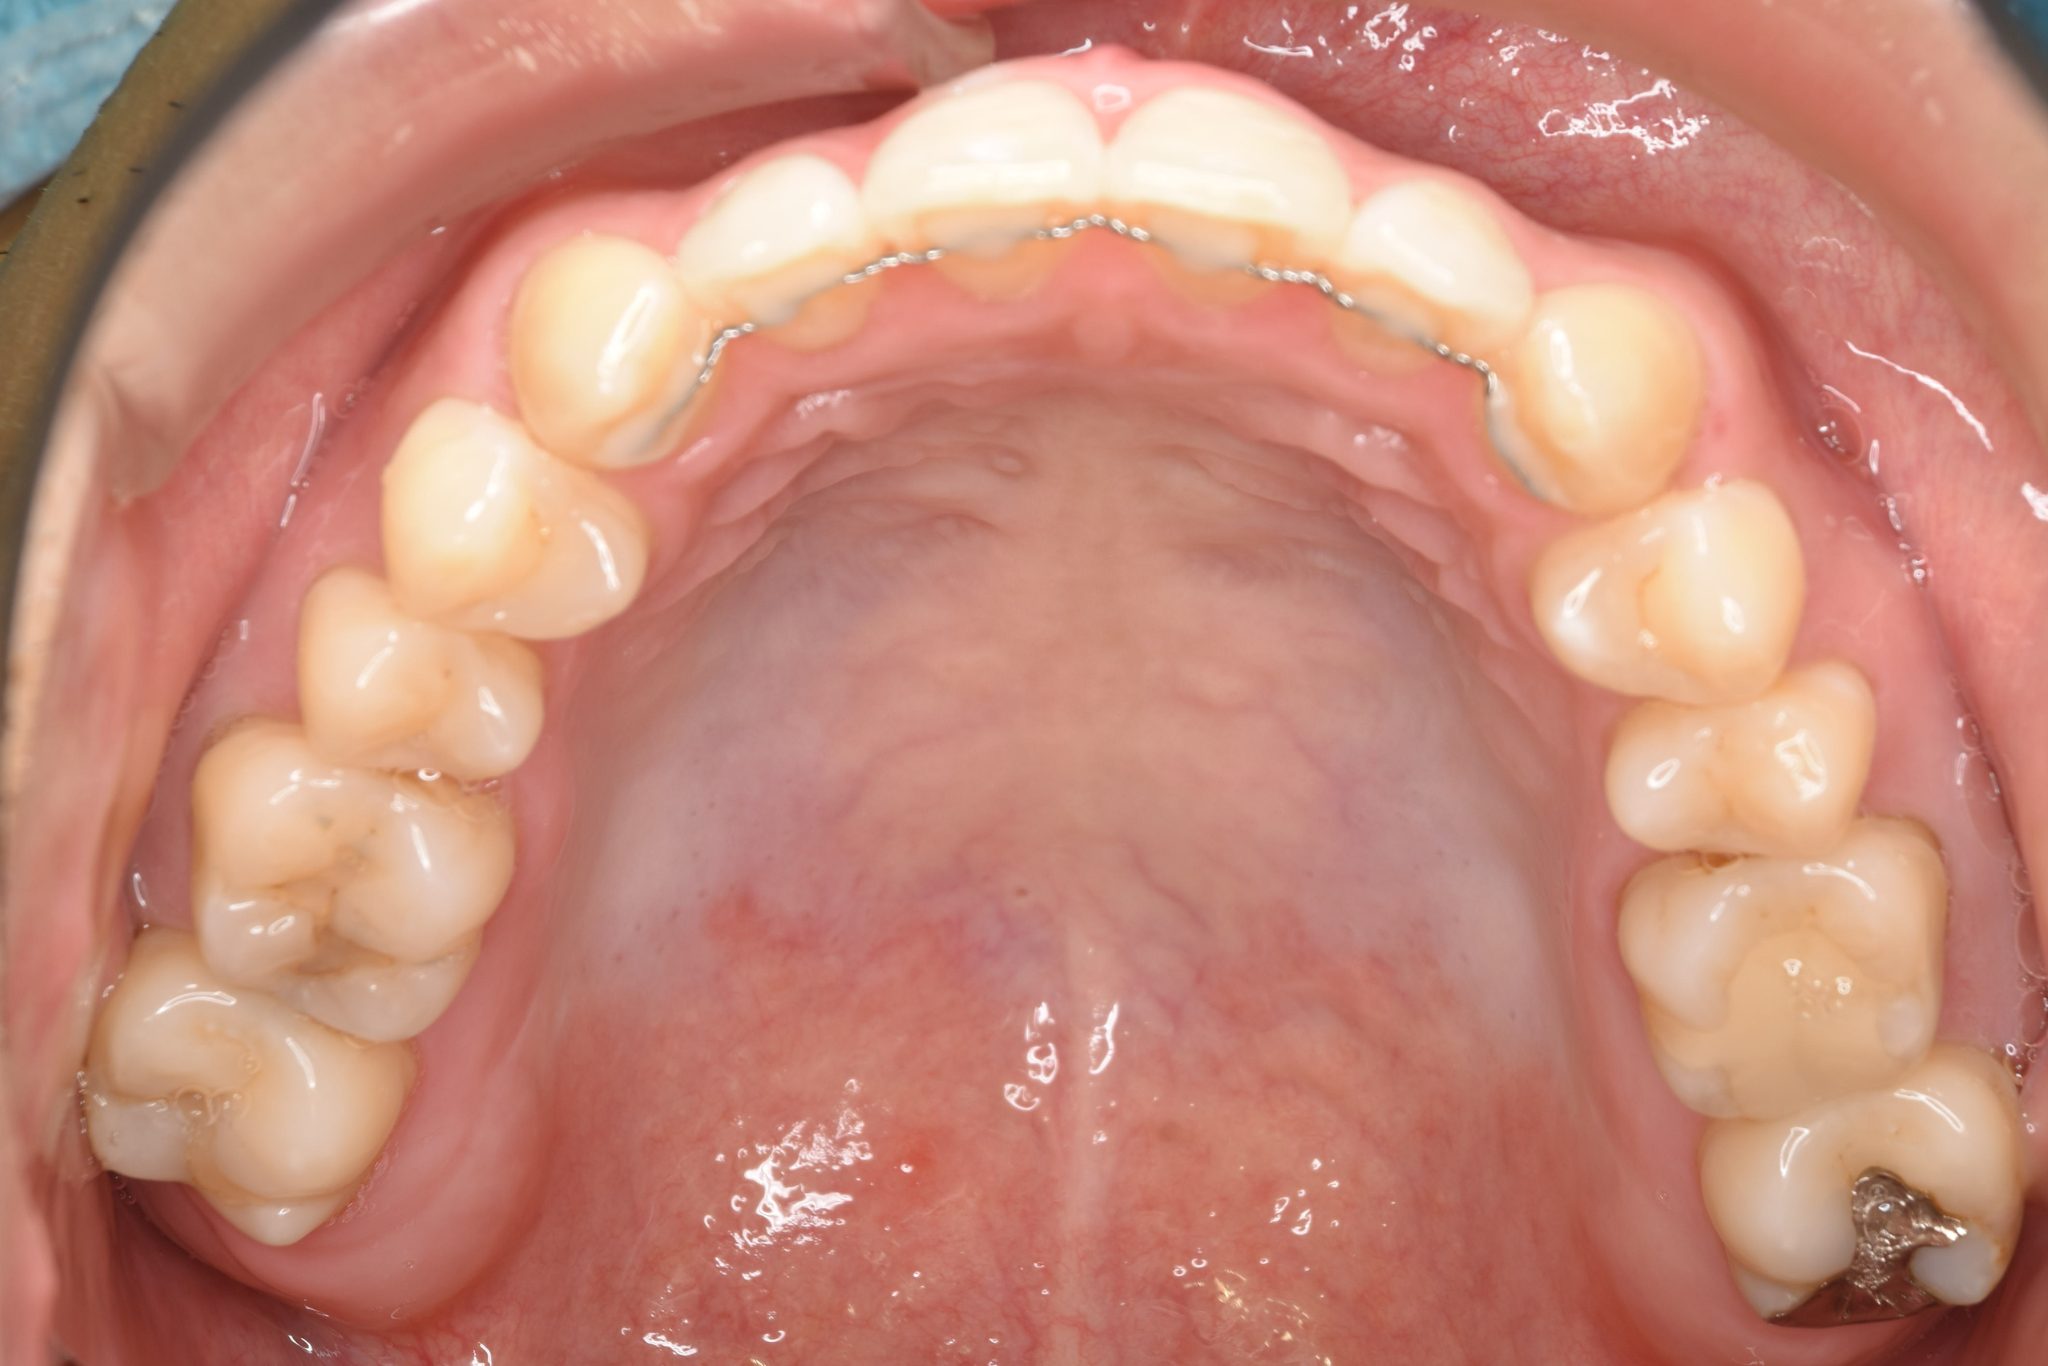

アフター

ワイヤー矯正治療|症例_495

施術内容 MSEと下顎リンガルアーチを用いて上下顎骨を拡大した。

その後マルチブラケット装置とミニインプラントを用いて

非抜歯で歯牙を配列し、良好な咬合を獲得した。

治癒期間 2年1か月間